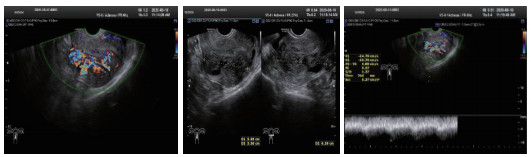

所有患者治疗前行TVDU诊断(图 1),25名诊断UAVF,最终经DSA确诊34名,超声诊断UAVF敏感率为74%,特异率为100%。

| 图 1 经阴道的多普勒超声下UAVF特征性表现 |

TVDU为疾病初筛的手段,敏感度可达74%,特异度100%,可以早期诊断UAVF [11-12]。超声下UAVF特征性表现为无回声区内有丰富红蓝镶嵌血流信号充填,呈“马赛克”或“湖泊样”改变,典型者见静脉血流动脉化表现[12-13]。见图 1。